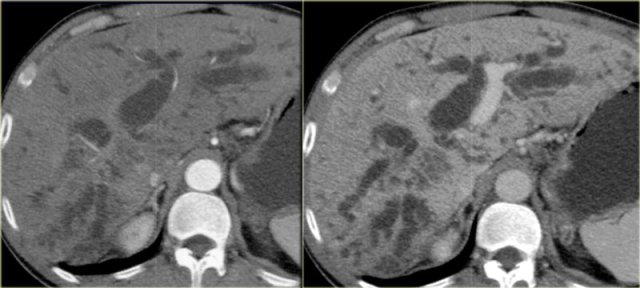

On the left a patient with more severe disease.

We can see mild bile duct dilatation with a discontinuous pattern.

On the left a patient with more pronounced CT findings.

Study the image and then continue reading.

The findings are:

- Discontinuous dilatation

- Bile wall thickening at the level of the porta hepatis

- Lymphadenopathy